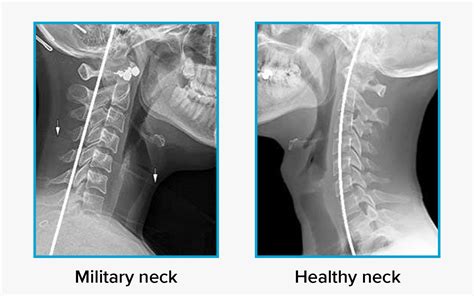

Walter Jackson Blog